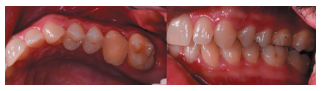

Caso clínico: se presenta el caso de un varón de 28 años, que acudió a consulta por la presencia de unos restos radiculares en localización de primer molar superior izquierdo. Se realizó un autotrasplante dental, siendo el diente donante el tercer molar superior izquierdo, que se trasplantó al alveolo del primer molar, mostrando buena evolución clínica y radiográfi ca.

Clinical case: a clinical case of a 28-yearold man is presented, who went to dental clinic for removal of left fi rst molar roots. An autotransplant was performed using left third molar as donor tooth, which was transplanted into fi rst molar alveolus, showing promising clinical and radiographic evolution.

Por tanto, debido a las altas tasas de éxito descritas en la literatura, el objetivo del presente caso clínico es evaluar clínica y radiográficamente la realización de un autotrasplante con el ápice cerrado, para reponer un primer molar superior izquierdo, como alternativa terapéutica a la colocación de un implante en un paciente adulto.